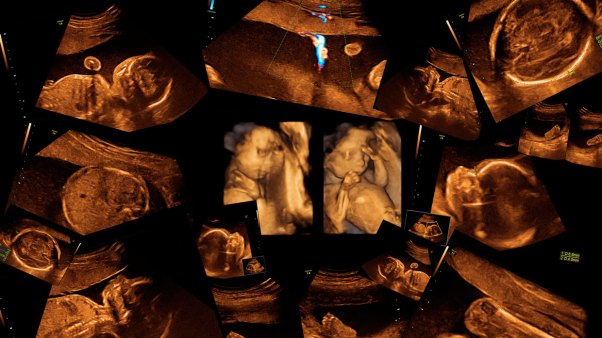

#DefundPP: From Hashtags to Healing

Leading your church in the fight for life.